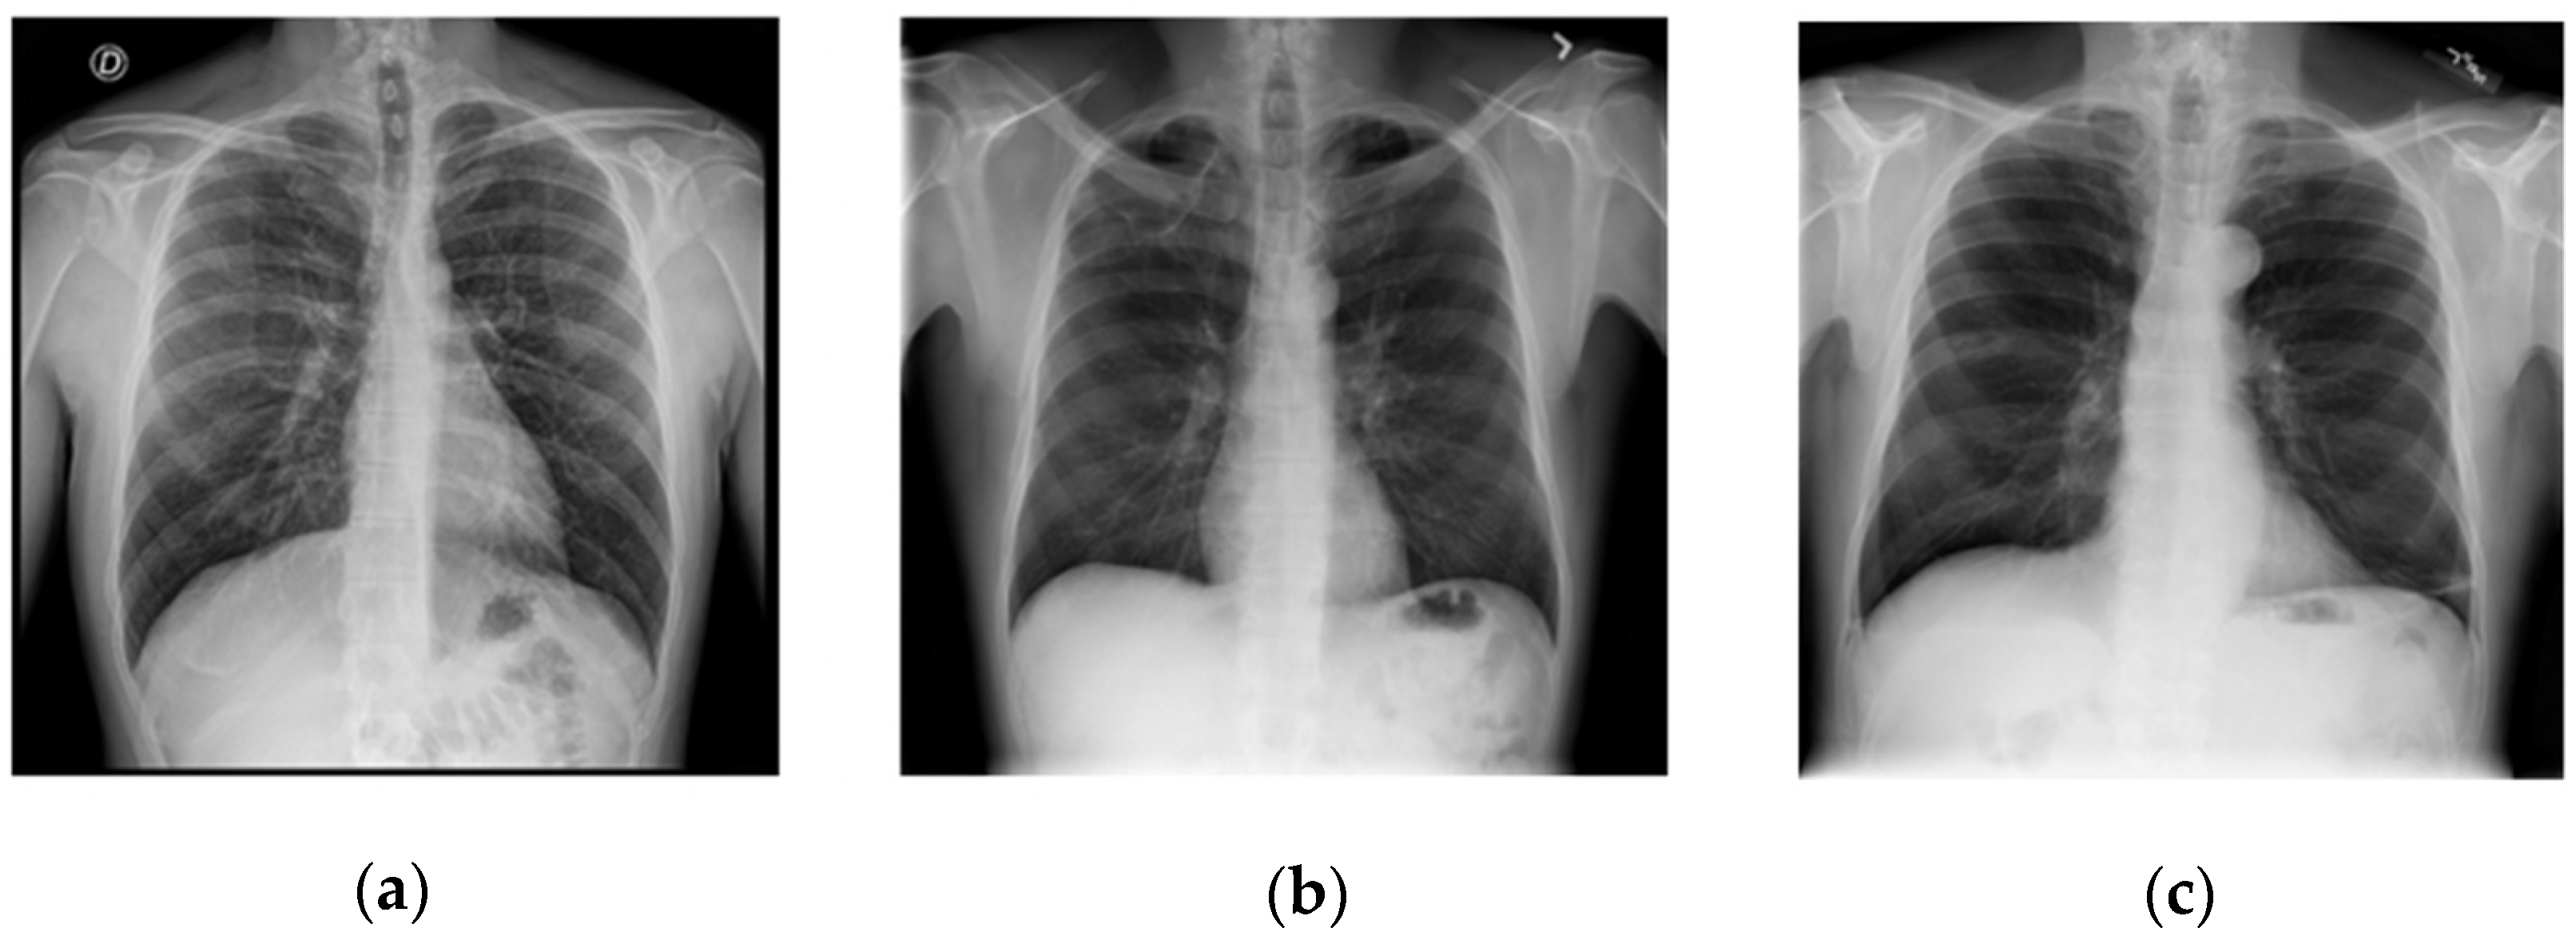

Mathematics Free FullText Fast COVID19 and Pneumonia Covid Chest X Ray Dataset Github  Covidx dataset | papers with code. We also introduce covidx, an open access benchmark dataset that we generated comprising of 13,975. There are 517 cases of covid. Covid Chest X Ray Dataset Github.